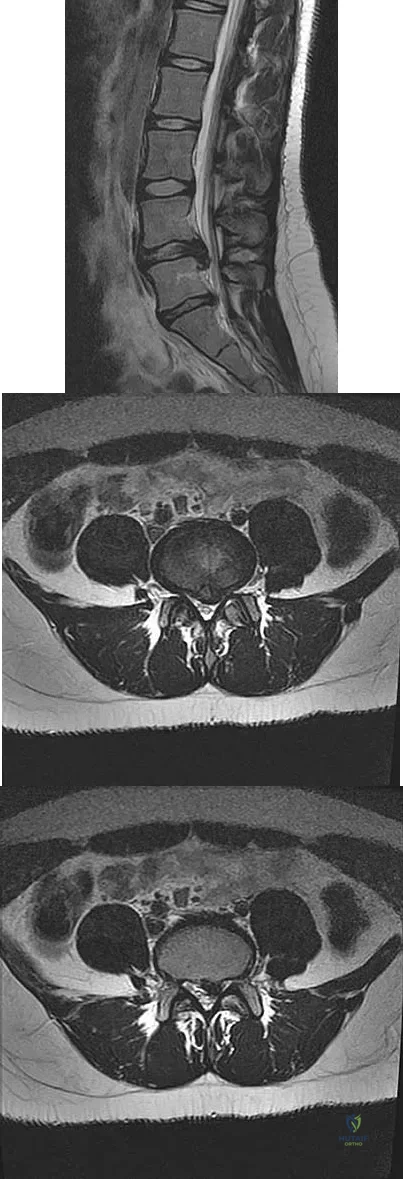

Question 35

A 50-year-old man with no history of trauma reports new-onset back pain after doing some yard work the previous day. He reports pain radiating down his leg posteriorly and into the first dorsal web space of his foot. MRI scans are shown in Figures 3a through 3c. What nerve root is affected?

Explanation